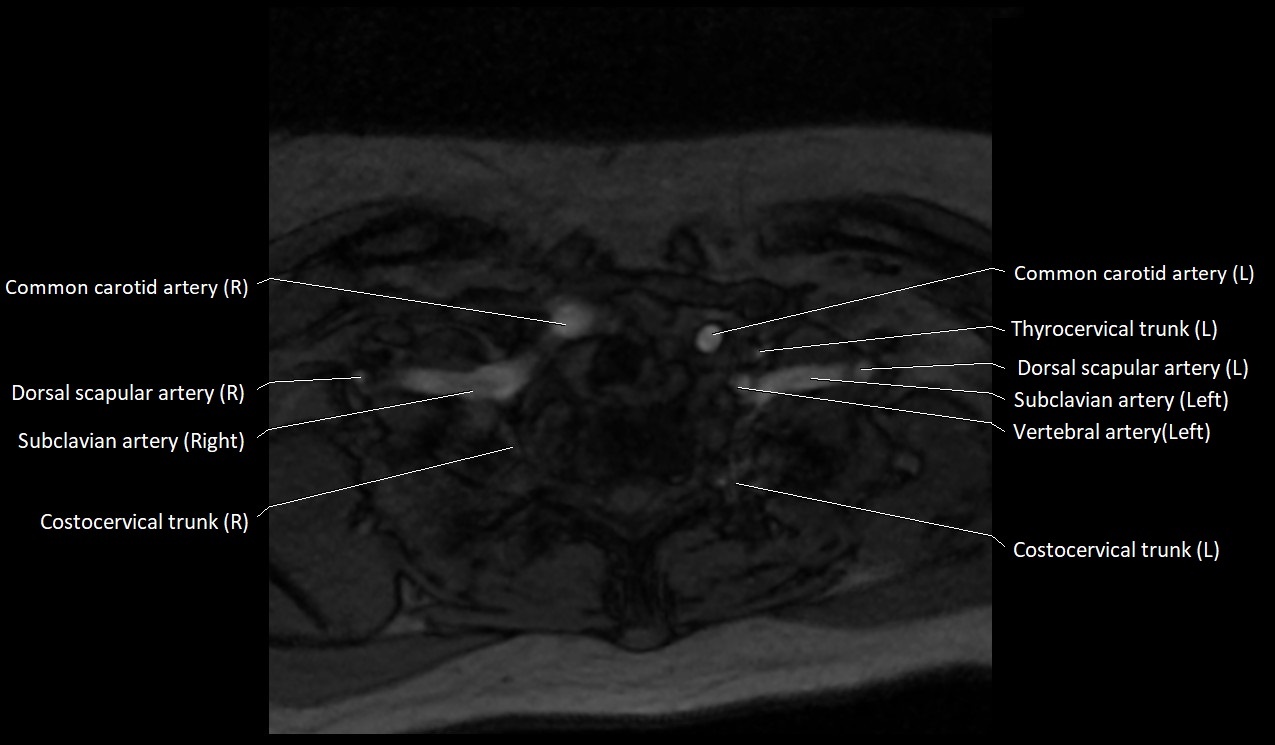

MRI images

image